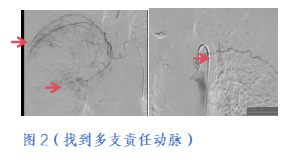

术中Z先生积极配合,胡乃东主任、陈光利主任全神贯注寻找到多支支气管动脉、肋间动脉及内乳动脉,发现肿瘤显影,栓塞责任血管(如图2),术后患者咳嗽、咳痰的颜色已明显转淡,术后第一天晨起查房,Z先生激动的告诉胡主任,“咳痰的颜色一点血都没了,输液多天都没有止住的血,微创介入治疗一次就立竿见影,也太神奇了”。胡主任点点头,并继续叮嘱他术后注意事项,关注贫血指标变化,随后继续规律化疗治疗肿瘤。